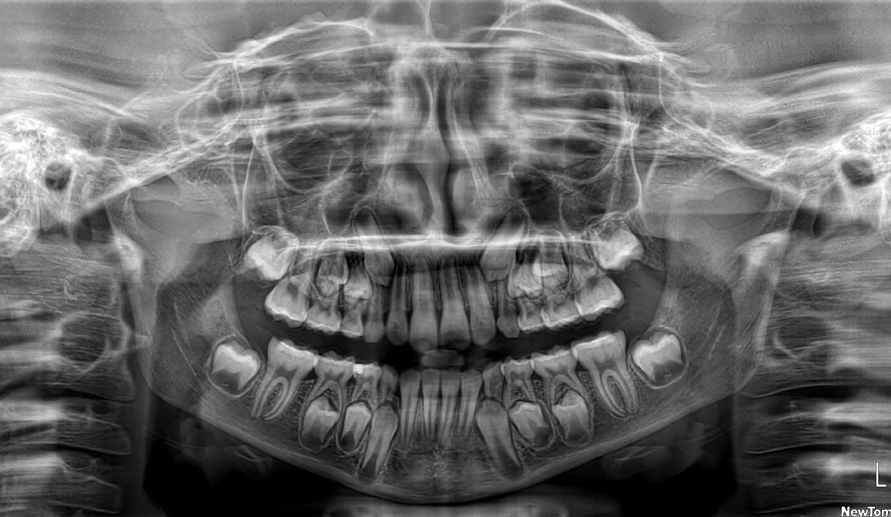

The patient presented with a skeletal Class I relationship and a mesofacial growth pattern, indicating balanced sagittal and vertical skeletal proportions. Dental examination revealed a Class I molar and canine relationship bilaterally. The patient was in the mixed dentition phase. Significant dental crowding was observed in both arches, consistent with a dentoalveolar discrepancy. Midline deviations were present, affecting dental symmetry and occlusal harmony. The maxillary lateral incisors were in crossbite, contributing to anterior transverse discrepancy and functional imbalance.

Periodontal evaluation revealed early signs of periodontal disease, primarily affecting tooth 41. Radiographic assessment demonstrated root convergence of teeth 11 and 21, indicating compromised root parallelism. Overall, the initial presentation was characterized by dentoalveolar crowding, transverse discrepancies, occlusal asymmetries, and early periodontal involvement within an otherwise favorable skeletal framework, requiring a carefully planned orthodontic approach to ensure functional stability and periodontal preservation.